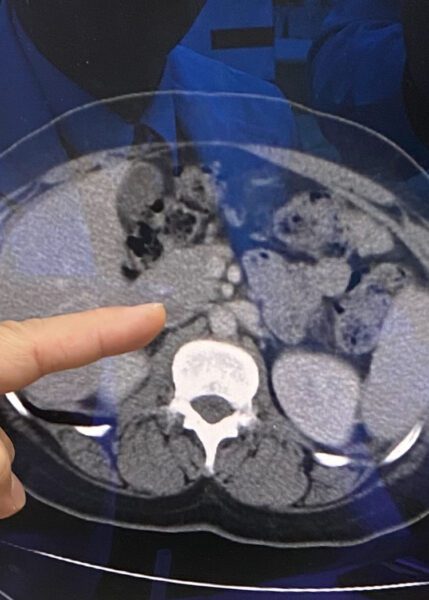

賴金湖主任說,這名患者到心臟外科門診前,已在其他醫院的婦產科及泌尿外科等門診反反覆覆檢查一段時間,做了一連串檢查,也做了電腦斷層及核磁共振還是沒有確定診斷,碾轉來到員榮心臟外科門診,才發現是少見的「胡桃鉗症候群」,就是左側腎靜脈被主動脈及下腸繫膜動脈的夾角壓迫,導致左側腎靜脈及左側骨盆卵巢靜脈回流阻力增加而產生症狀 。

賴金湖與病患討論並解釋治療方式,最後決定實施微創導管氣球擴張術及自費腎靜脈支架置放;術中以血管內超音波診斷,確定有明顯外在壓迫,並測量下腔靜脈與左腎靜脈的壓力差大於等於2 mmHg,便以低壓力的氣球先作擴張,仍然存在大於等於2 mmHg壓力差,再與病患討論,便利用右頸靜脈導管,順利將腎靜脈支架置放在壓迫處,完全改善左側腎靜脈血液回流,歷經三個月門診追蹤後,病人下肢腫脹及骨盆痠痛的症狀,很快改善。